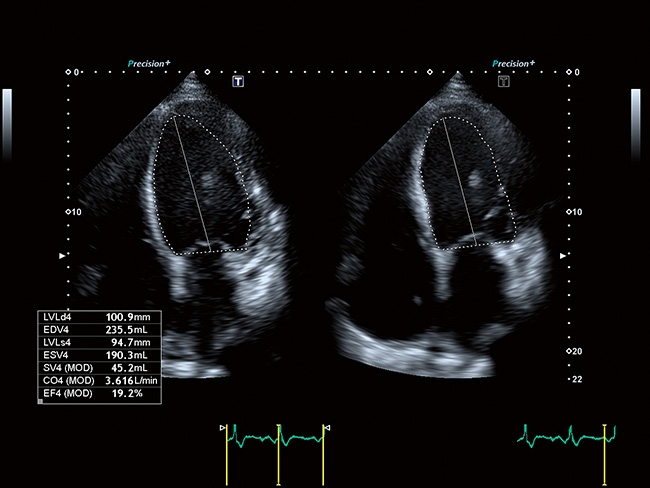

Стационарная цифровая ультразвуковая система Toshiba (Canon) a550. Современные технологии визуализации, цифровое формирование луча, удобная для работы панель. Характеристики, удовлетворяющие требованиям к системам УЗИ экспертного класса.

Отличная цветопередача с высокой детализацией и четкостью изображения. Устройство подходит для профессионального использования в частных кабинетах и крупных медицинских центрах. Комплектация сканера применима для самых разных исследований. Широкий диапазон прикладного клинического программного обеспечения высокоэффективен для общих исследований, сердечно-сосудистых, гинекологических, ортопедических, урологических.

Aplio a550 может работать с линейным матричным датчиком и поддерживает новейшие монокристаллические датчики. Также Aplio a550 поддерживает большое количество дополнительных опций, таких как - SMI, Компрессионная эластография, Эластография сдвижной волны, Smart Fusion, исследования с использованием контраста (CEUS), 3D реконструкции в реальном времени (4D), функции автоматической оценки подвижности миокарда и фракции выброса.